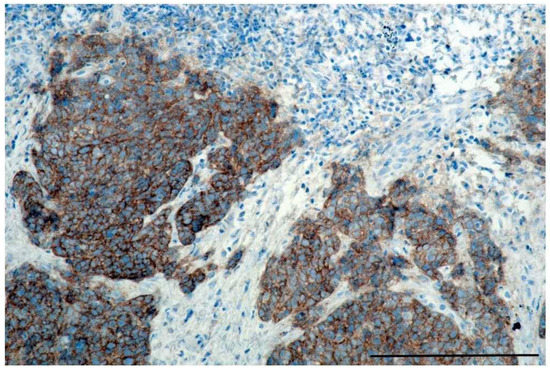

4.5. IHC